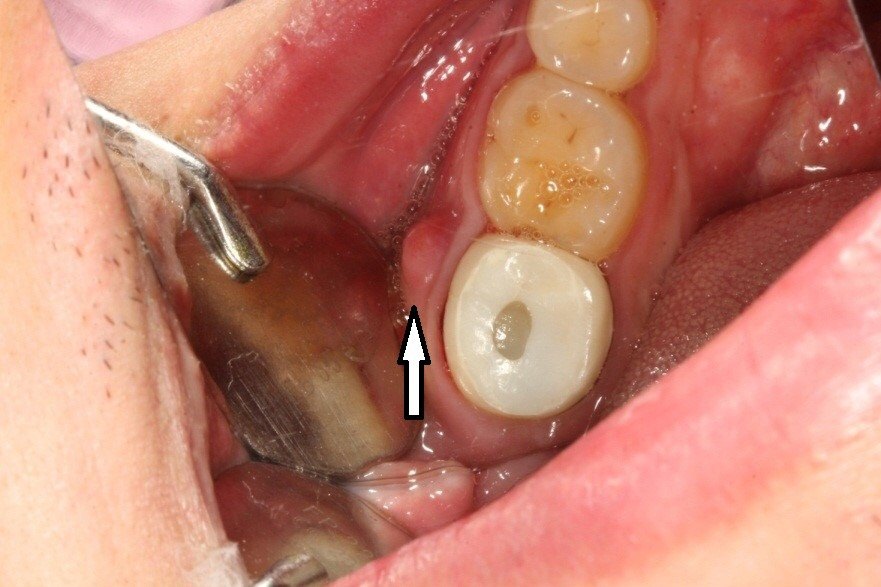

图2: 检查:全瓷牙冠修复,牙齿松动一度,叩痛明显,牙龈有脓肿。

图3: X线:显示牙冠的牙齿牙根纵向折断。处理方法:拔除。、